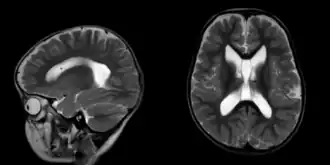

Seizure disorders are common,[3] and may include generalized tonic–clonic, absence, rolandic and febrile seizures.[4] Neuroimaging usually reveals benign brain anomalies.[5] Other neurodevelopmental findings include mildly decreased muscle tone, poor motor coordination and unusual walking. Feeding difficulties—made worse by decreased tone of muscles—begin in infancy and may lead to failure to thrive.[6] Children can also experience reflux and constipation.[7] Heart defects such as ventricular septal defect and lung conditions like tracheomalacia occur rarely.[1]

Growth parameters and milestones are regularly evaluated to monitor progress. Early intervention is often necessary, and involves physical therapy to improve motor skills, occupational therapy to enhance daily functioning and speech therapy to support language development. An Individualized Education Program can be used to tailor education to a child's cognitive profile and address specific learning needs. Individuals who have experienced seizures may undergo further evaluation with electroencephalography and MR brain.[1] Anticonvulsant medications may be needed based on clinical findings.[2] In some cases, temporary feeding tube placement has been required due to failure to thrive and persistent feeding difficulties.[11]